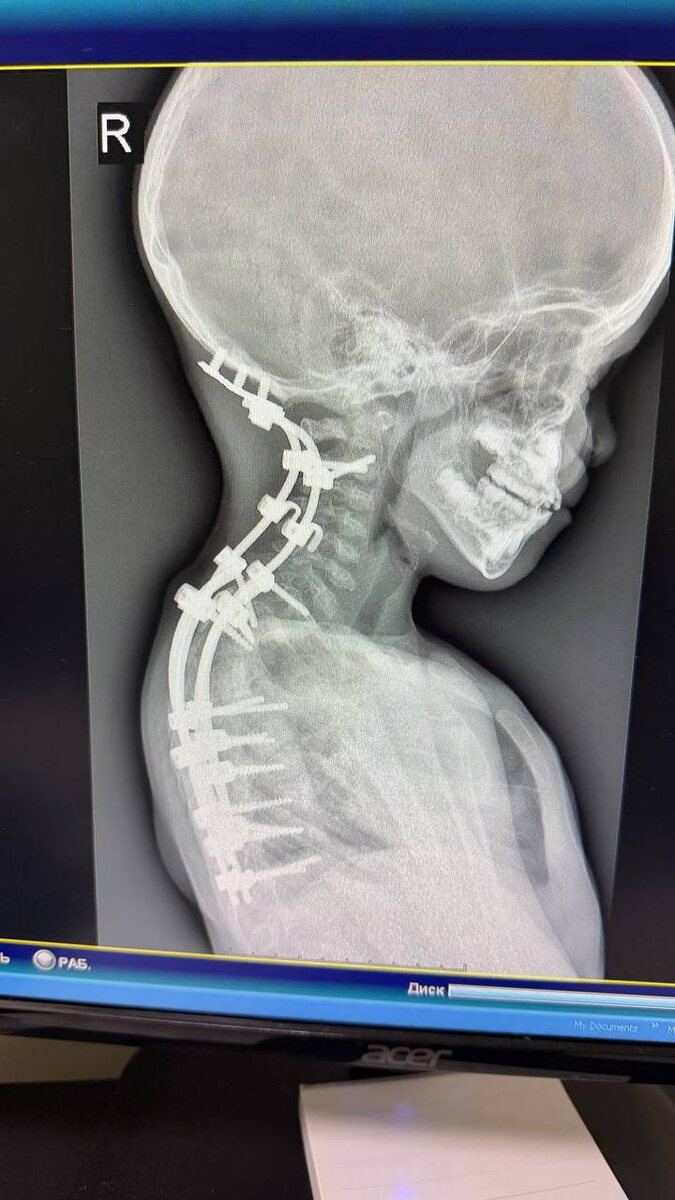

Отходит от головы 😭